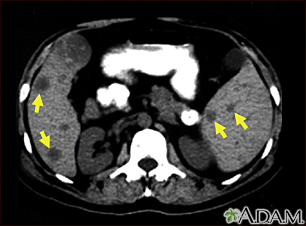

Spleen and liver metastases – CT scan